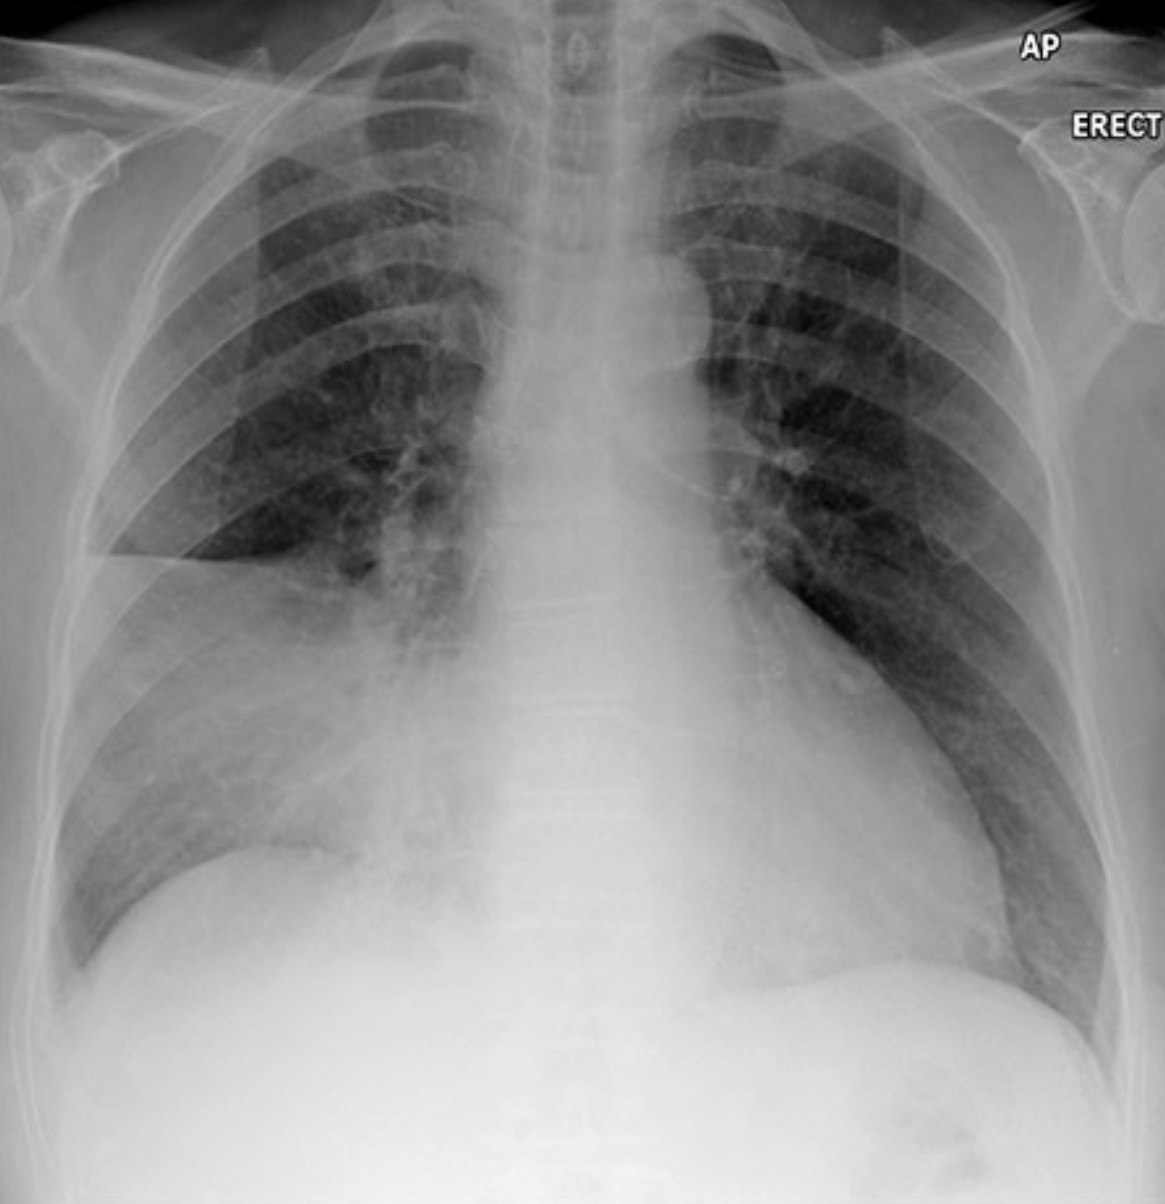

Describe the abnormality demonstrated.

Right-sided flail chest involving the third to ninth right posterior/lateral ribs

Comminuted right clavicle fracture (inferior displacement?)

Significant right-sided pleural effusion

Collapse of right lower lobe